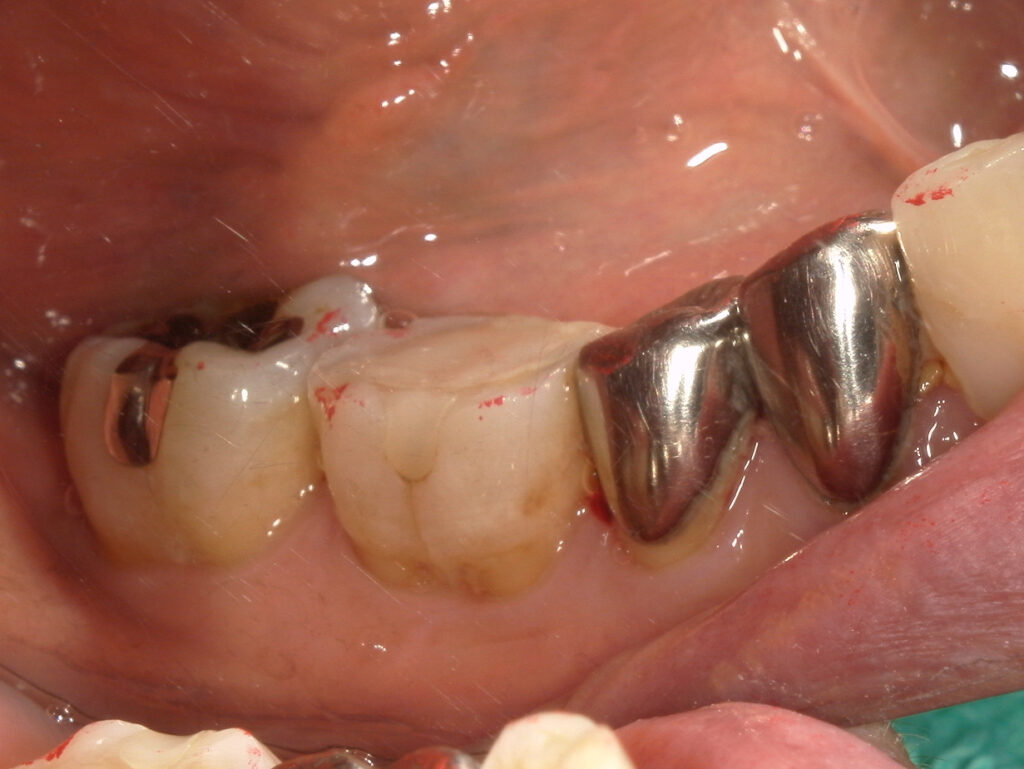

↑ブルーラジカル治療後

●治療内容

右下5,7 ブルーラジカル処置

●治療期間

R7.10.17 右下5,7ブルーラジカル処置

R7.2.20 再評価

●費用

¥55,000

●来院回数

ブルーラジカル治療では3回